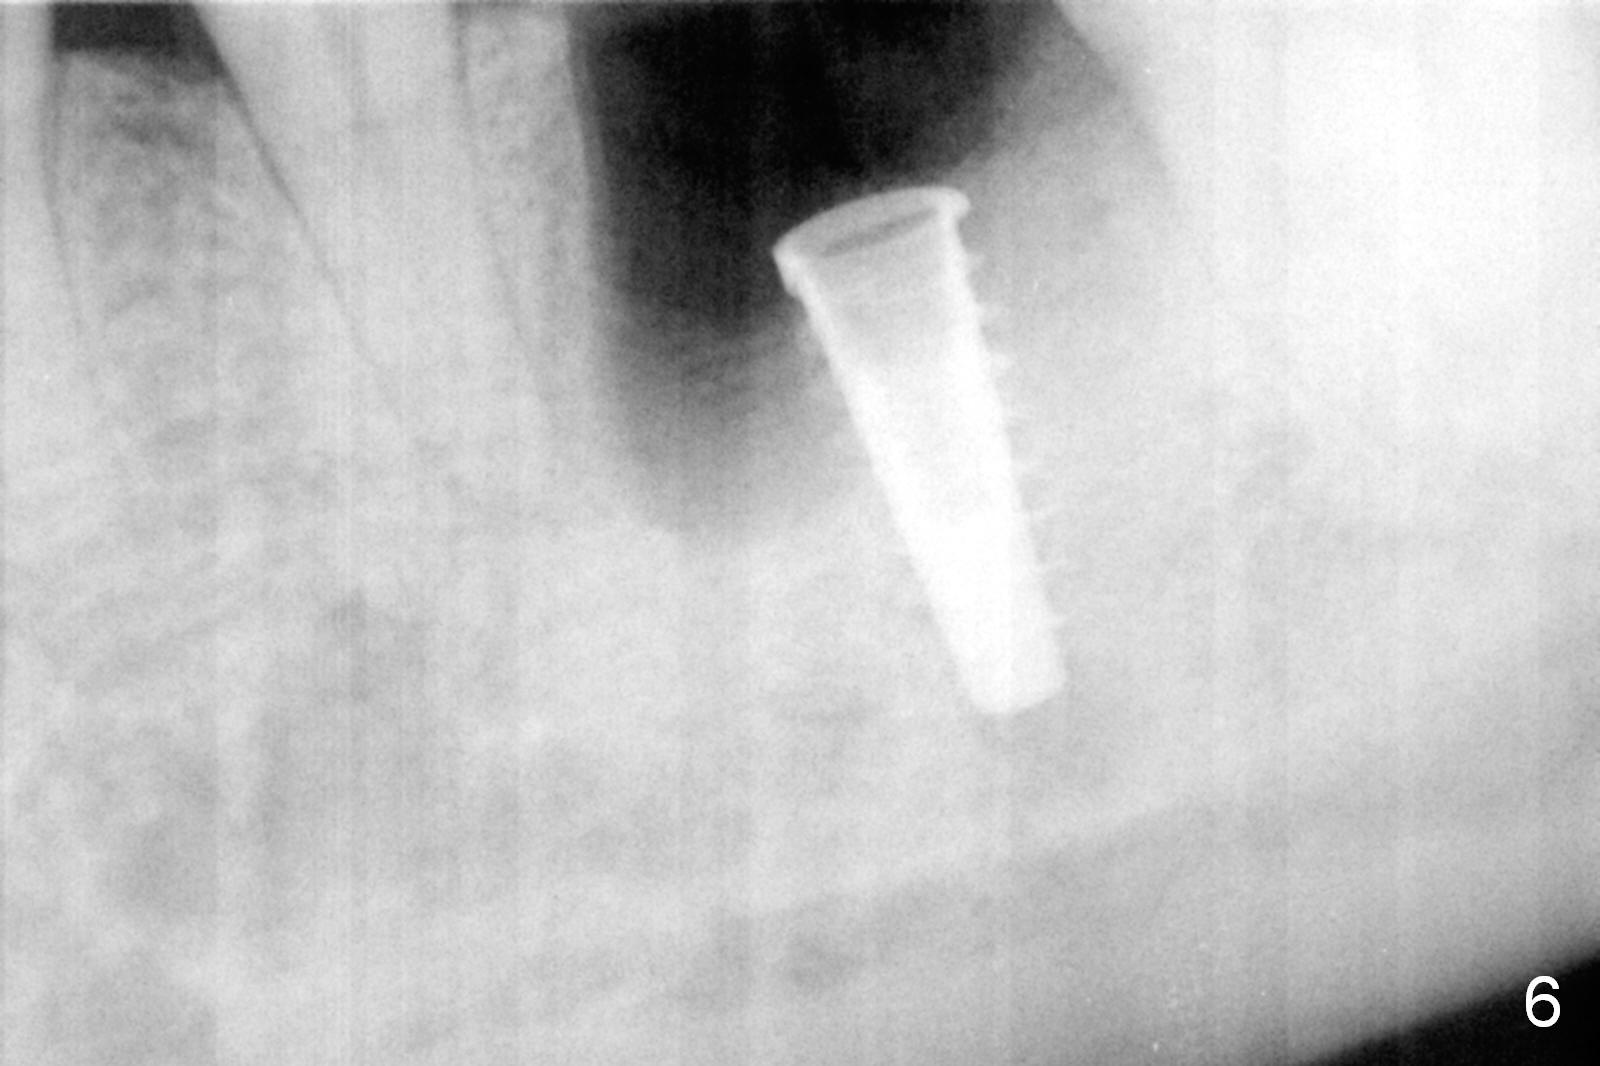

The asymptomatic tooth (#19) has a midbuccal fistula (Fig.1 <). The mesiobuccal pocket is 10 mm with purulent discharge from the sulcus (Fig.2,3). The mesiobuccal wall defect is confirmed when the tooth is extracted. Osteotomy is initiated lingually in the septum following septal crestoplasty (flattening) (Fig.4: using 1.6 mm drill for 9 mm). Since the lingual portion of the osteotomy is higher, it is difficult to use drill with stopper. For the narrow septum osteotomy, multiple drills are used sequentially (Fig.5 after 4.3 mm drill). A 4.5x11 mm dummy implant is placed (Fig.6) apparently too deep. When a 5x11 mm IBS implant is being placed, the depth is tightly controlled (Fig.7). The implant is apical to the lingual crest, whereas there is ~ 2 mm implant exposure buccally. That is, there is a large gap mesiobuccally (Fig.8), which is filled with .5-1.5 mm allograft (Fig.9 *). A 6.5x5.7(3) mm abutment (A) is placed and trimmed for an immediate provisional (Fig.10 P). The lacerated buccal gingiva is sutured as well as application of Perio Glue.